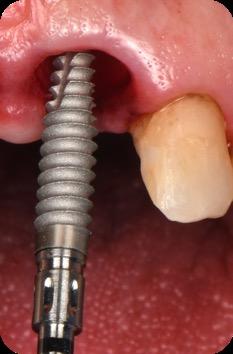

BioHorizons has introduced a new implant system that combines the advanced thread design of the Tapered Pro with the precision and stability of the Conelog conical connection. This integration delivers enhanced surgical handling, improved primary stability, and long-term biological benefits, supporting better patient outcomes in both aesthetic and functional zones.

This case was performed by Dr Homa Zadeh, DDS, PhD, a respected leader in periodontology and implant dentistry. Dr Zadeh’s approach emphasizes biologically driven protocols and evidence-based techniques, making this case a strong example of clinical excellence using the Tapered Pro Conical system. It involves the replacement of two front anterior teeth after they fractured off and the full restoration process.

Fig 5. Central incisors extracted using minimally invasive protocol. Alveolar bone and gingival tissues were intact after extraction

Fig 6. BioHorizons Tapered Pro Conical implants of 3.8 x 15mm placed according to the plan.

Fig 7. Implants immediately after installation.